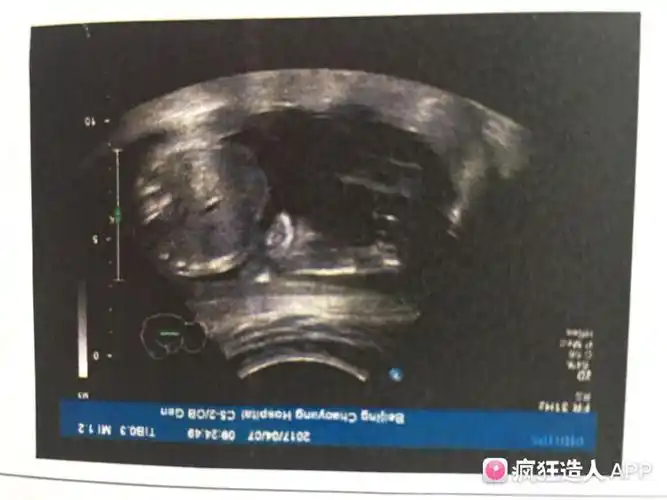

给你看个图你就明白了…放大看两腿之间有三个点,三条白线,男宝是没有

这个是三条线吗是不是女宝

[试管婴儿]b 超图 大神帮看看是传说中的三条线么?

转帖哦,,精心收集男宝女宝b超图片数张!附b超特徵总结!